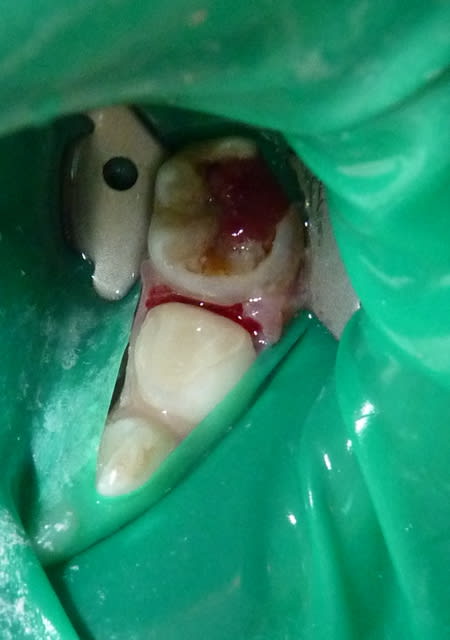

Dans le cas ci-dessous, la 1ère photo est prise après début d’éviction carieuse : sur la 4, on voit déjà la pulpe par transparence. Les tubuli dentinaires d'une dent temporaire sont beaucoup plus larges et nombreux que sur une dent permanente. Ainsi, une carie dentinaire infecte très rapidement la pulpe camérale. Faire une restauration sans pulpotomie dans ce cas aurait probablement abouti à une nécrose à moyen terme.

P1010955 lkrpua - Eugenol

P1010959 qtf3fy - Eugenol

P1010962 ddzmfk - Eugenol

P1010966 tt9pyf - Eugenol

P1010974 bokjpr - Eugenol